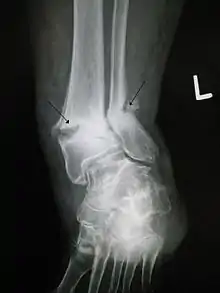

Classification

(a) closed fracture

(b) open fracture

(c) transverse fracture

(d) spiral fracture

(e) comminuted fracture

(f) impacted fracture

(g) greenstick fracture

(h) oblique fracture

In orthopedic medicine, fractures are classified in various ways. Historically they are named after the physician who first described the fracture conditions, however, there are more systematic classifications as well.